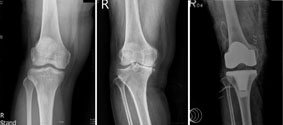

退化性關節炎(相關圖片)           1                       2                           3

1.輕微退化性關節炎

2.嚴重退化性關節炎

3.手術後(人工關節置換)